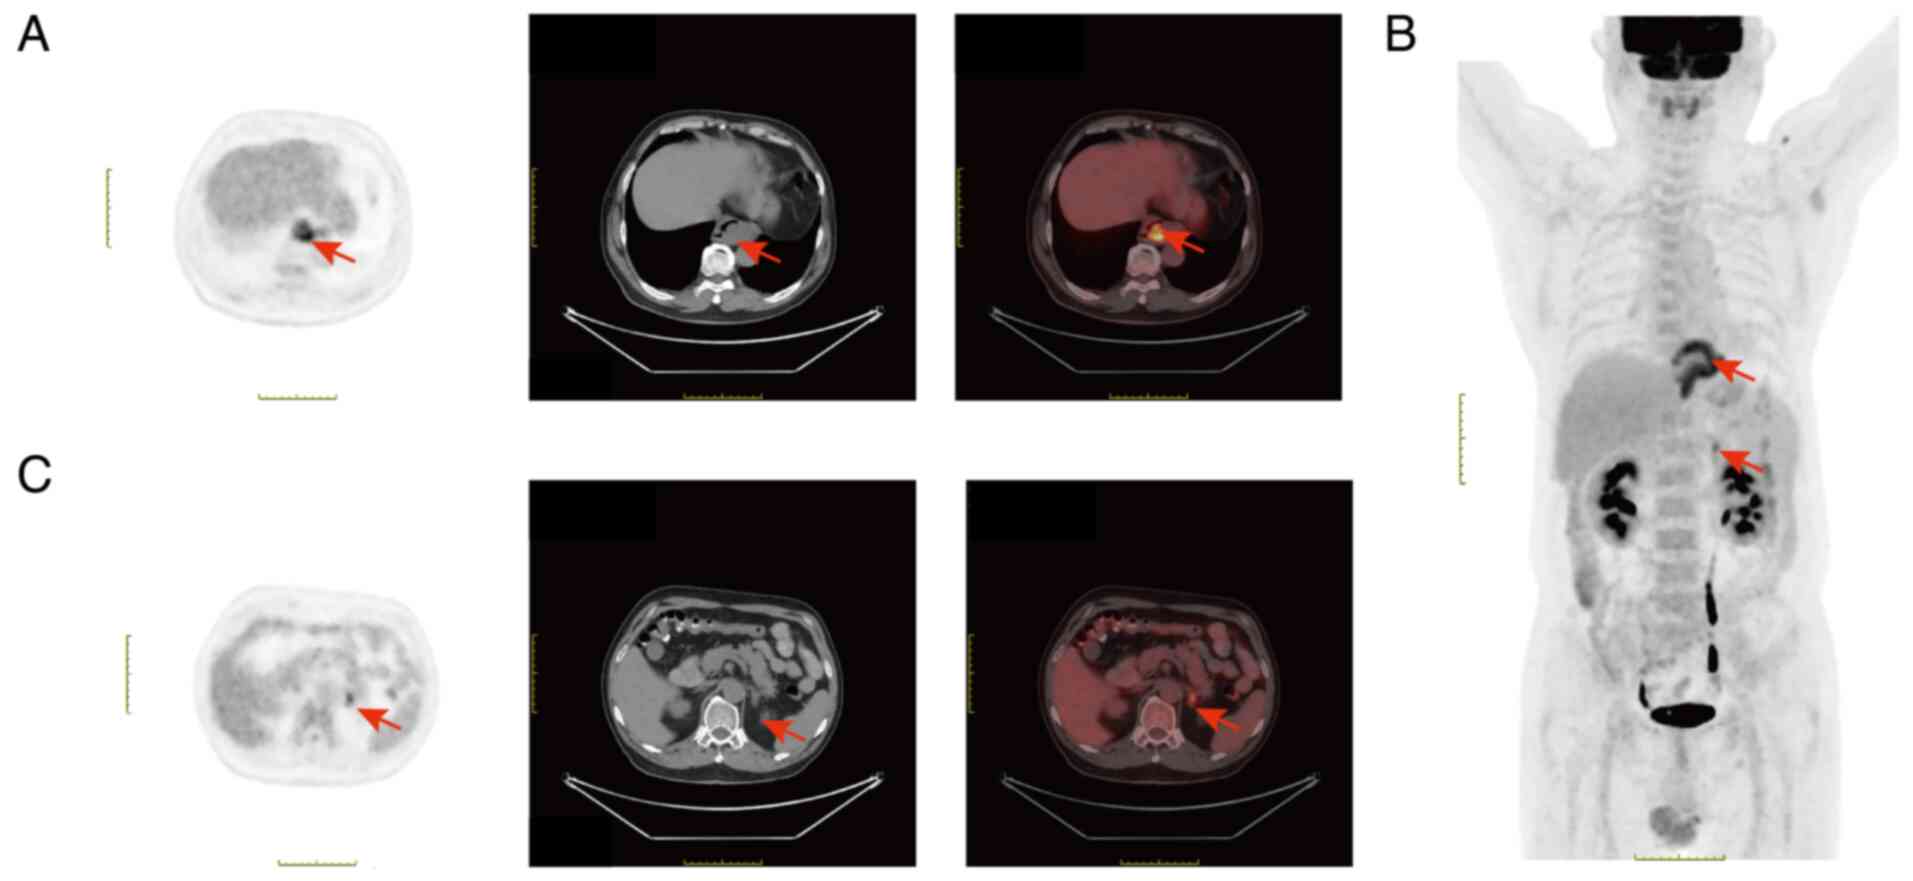

Leiomyoma is a benign muscular abnormality that commonly occurs in the middle and distal third of the esophagus, leading to thickening of the esophageal wall and subsequent esophageal luminal narrowing. Notably, esophageal leiomyoma often does not show increased 18F-fluorodeoxyglucose (FDG) uptake on positron emission tomography (PET). The present study described a case of esophageal leiomyoma combined with adrenal adenoma. Results of the PET-computed tomography analysis revealed that FDG metabolism was increased in the lower segment of the esophagus and the left adrenal gland, with maximum standardized uptake values of 6.5 and 4.1, respectively. Therefore, initially, the patient was diagnosed with an esophageal malignant tumor with left adrenal metastasis. Open surgery was performed for complete removal of the lesions, and results of a routine pathological analysis revealed esophageal leiomyoma combined with adrenal cortical adenoma. The present study indicates that to avoid unnecessary surgeries, esophageal leiomyoma and adrenal cortical adenoma should be diagnosed through a comprehensive assessment with endoscopy, endoscopic ultrasound, computed tomography, magnetic resonance imaging and tissue sample pathology, not just PET.

Figure 1